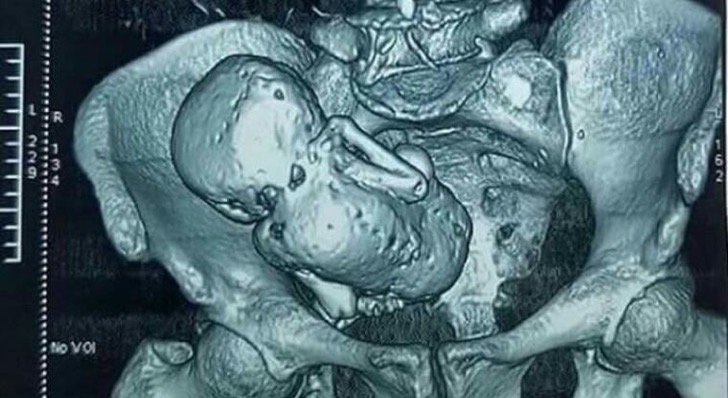

Ecografiile și examinările amănunțite au semnalat un amănunt șocant în pântecele ei era un făt complet pietrificat... de 30 de ani.

Până după 30 de ani, când din abdomen i-a fost extirpat un făt pietrificat.

În acele vremuri, puțini auziseră de boala numită Litopiedion sau ”Bebelușul de Piatră”, un fenomen foarte rar (1.3-3% din sarcinile abdominale avansate) care apare atunci cand un fetus moare in timpul unei sarcini ectopice (implantarea embrionului in orice alt tesut in afara de cel al peretelui uterin).

El este prea mare pentru a fi resorbit de catre corpul matern, ramane in cavitatea abdominala si incepe sa se calcifieze subcutanat (proces ce apara mama de tesutul mort si previne infectia).